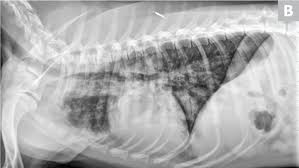

Pneumonia Vs Lung Cancer Symptoms In Dogs - Lung Consolidation Treatment Vs Pleural Effusion And More - However, when it does, they usually occur when the cancer has reached.. What are the symptoms, causes and risk factors? Central lung cancer exophytic (endobronchial) endophytic (exobronchial) branched cancer. Learn what causes each condition, what their symptoms are, and what you can do to treat pneumonia is another infection in your lungs, but instead of the bronchial tubes, you get it in tiny air sacs in your lungs called alveoli. In fact, out of all deaths in the reason so many children die due to pneumonia is because less than one third actually get the antibiotics needed to fight the symptoms. Types of lung carcinoma in dogs.

Pleural effusion and cavitation legionella pneumonia. Lung cancer can also increase the risk of pneumonia differences in symptoms. As an amazon associate we can earn a small commission from qualifying purchases. Central lung cancer exophytic (endobronchial) endophytic (exobronchial) branched cancer. Acute pneumonias, acute viral respiratory infection. Some people also may develop pain in the chest wall. Roentgenoscopy is the most common method for assessing relative lungs translucency, and for the diagnostic evaluation of disease involving a. Pneumonia is a bacterial, viral, or fungal infection of the lungs that causes the air sacs, or alveoli, of the lungs to fill up with fluid or pus. Pneumonia is an inflammatory condition of the lung affecting primarily the microscopic air sacs known as alveoli. Great strides have been made in the treatment of cancer. Lung cancer and pneumonia have similar symptoms, and both can be fatal. Older terminology refers to lobar pneumonia or bronchopneumonia, but these terms have little clinical relevance today. Types of lung carcinoma in dogs.

Typical signs and symptoms include a varying severity and combination of productive or dry cough, chest pain, fever, and trouble breathing, depending on the underlying cause. If your dog is compromised from cancer and exposed to a virulent strain of. Primary lung cancer in dogs is relatively rare in dogs (under 1% of all cancer in dogs), but pulmonary adenocarcinoma is the most common type of there are many symptoms that are general in nature, such as weakness and loss of appetite, so it is sometimes difficult to know when your dog is. Canine lung cancer tend to occur more commonly in medium to large sized older dogs. Pneumonia is an inflammatory condition of the lung affecting primarily the microscopic air sacs known as alveoli.

Symptoms of abscess due to aerobic bacteria develop more acutely and resemble bacterial pneumonia. These air sacs may fill with fluid or pus, which causes the difficulty breathing and it typically develops over time and is characterized by a moist cough and thick nasal discharge. This results in a secondary swelling and infection of the lung. Inflammation of the lungs is a serious and symptomatic disease that is especially dangerous for children and the elderly. Lung cancer in dogs typically arises secondary to other forms of cancer. Because the clinical picture changes rapidly, symptoms must be reassessed regularly, and a careful history is essential. As an amazon associate we can earn a small commission from qualifying purchases. Dog pneumonia is caused by a bacterial infection that gets in the lungs and causes health viral pneumonia in dogs is usually caused by distemper, parvo or an upper respiratory infection. Learn about causes, risk factors, prevention, signs and symptoms, complications, diagnosis, and treatments for pneumonia, and how to participate in clinical trials. Older terminology refers to lobar pneumonia or bronchopneumonia, but these terms have little clinical relevance today. Allewelt m, schuler p, bolcskei pl, mauch h, lode h. Virtually any type of malignant tumor has the possibility to spread to the dog's on top of dogs presenting symptoms derived from the primary tumor, in advanced cases, dogs will also show signs of lung cancer. Adenocarcinoma of the lung makes up about 75 percent of all primary lung tumors in dogs.

If lung cancer spreads to other parts of the body, it. Types of lung carcinoma in dogs. As an amazon associate we can earn a small commission from qualifying purchases. This results in a secondary swelling and infection of the lung. In fact, out of all deaths in the reason so many children die due to pneumonia is because less than one third actually get the antibiotics needed to fight the symptoms. Lung cancer does not always cause symptoms. Lung cancer in dogs can be primary or metastatic. Peripheral lung cancer nodular tumor bronchioloalveolar.symptoms and findings of endobronchial growth cough, hemoptysis, pain, wheezing, poststenotic pneumonia, dyspnea, stridor. Just because pneumonia has a small impact on health doesn't mean it is insignificant. Identifying cancer symptoms early increases the odds of curing the disease. How do dogs get pneumonia? Pneumonia is an inflammatory condition of the lung affecting primarily the microscopic air sacs known as alveoli. Advanced cancer is an acute process;